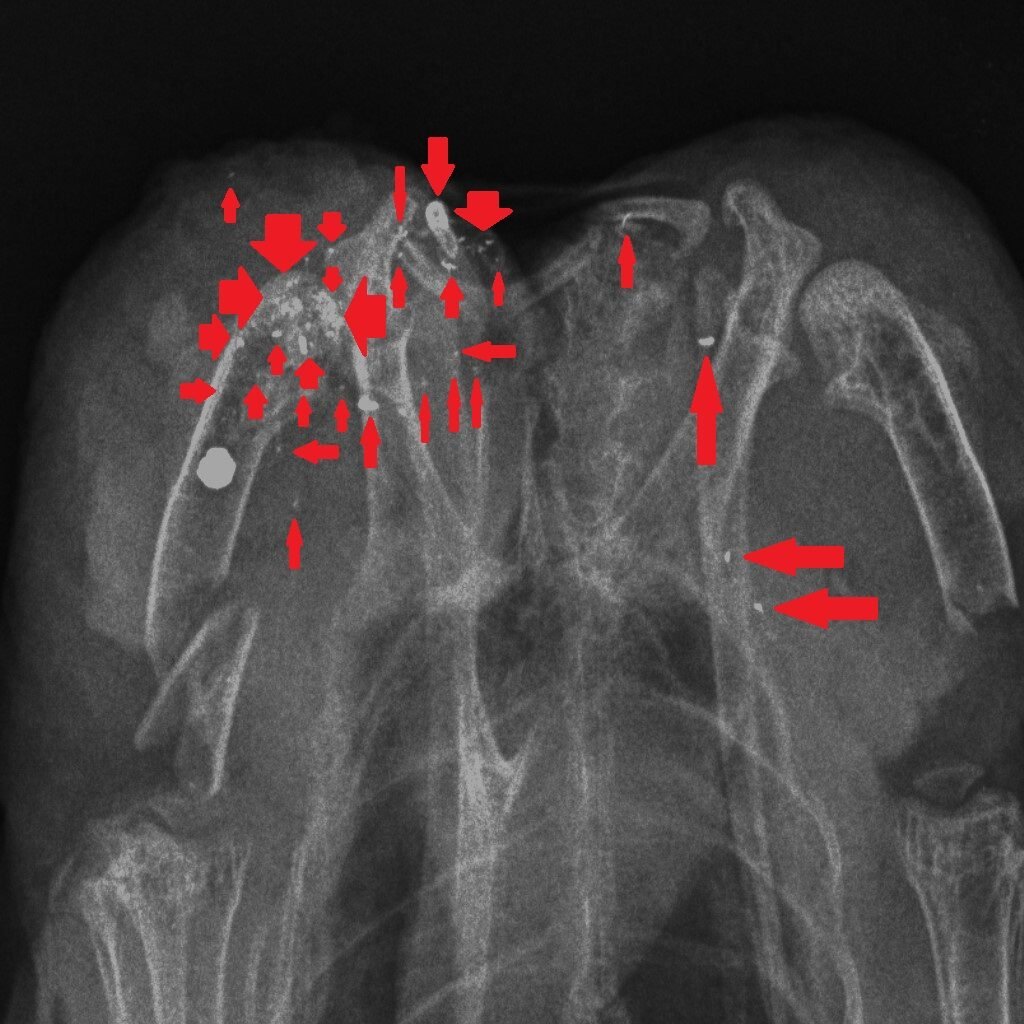

How could we reduce the risk of exposure to lead in game meat? It’s simple – stop shooting lead ammunition into animals that are destined for the human food chain. One of the useful properties of lead is that it is soft and malleable – that’s why, in the past, we have used it widely. But those same physical properties mean that lead passing through the flesh of a shot animal, hitting organs, soft tissue, bones and cartilage, shatters and tiny fragments of lead spread through the body of the animal. Here are three x-rays of shot birds that were bought in butcher’s shops and then x-rayed. The top x-ray is of a partridge and the other two are Red Grouse. Large white circular objects are lead shot. The green arrows point to fragments of bone and the red arrows indicate fragments of lead, from the shot, that have spread through the flesh.

Almost all of the fragments of lead are tiny – far too small to be detected in the cooking or eating process. Yes, you can spit out the almost-intact lead shot but you can’t get rid of the fragments. The lead analyses that have been done in studies cited above, and in our own, remove the lead shot and analyse the lead content of the meat after that removal. So when Sainsbury’s say that their game meat has no lead shot in it that’s good (although careful eating would remove those anyway) but they are not removing the tiny fragments of lead. So removing the almost intact lead shot particles is pretty irrelevant to the lead levels in the meat, as we will show you later this week…